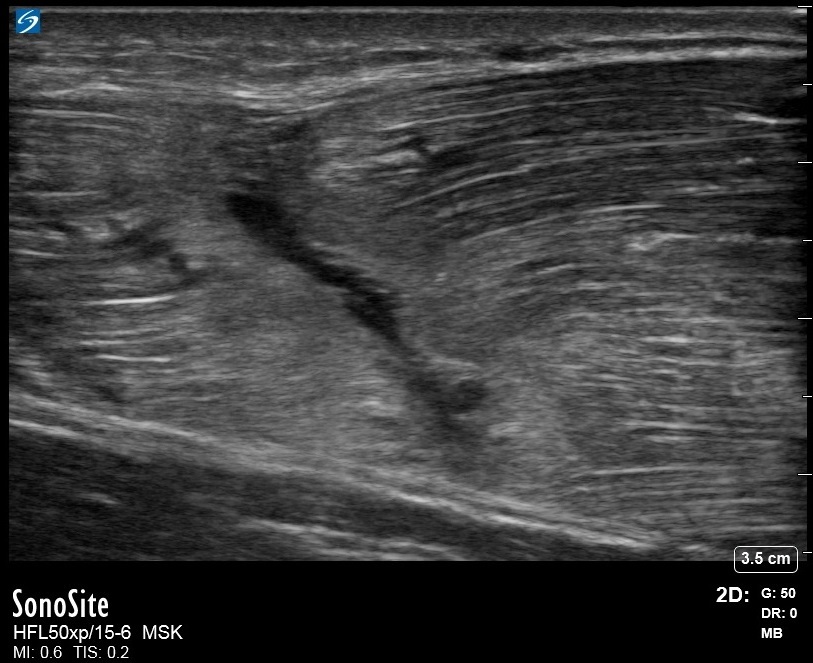

肩部撕裂三头肌图像